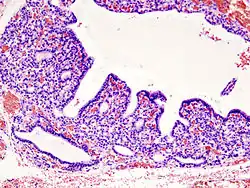

Involution - normal atrophy, e.g. thymus in adults, uterus in the older woman.